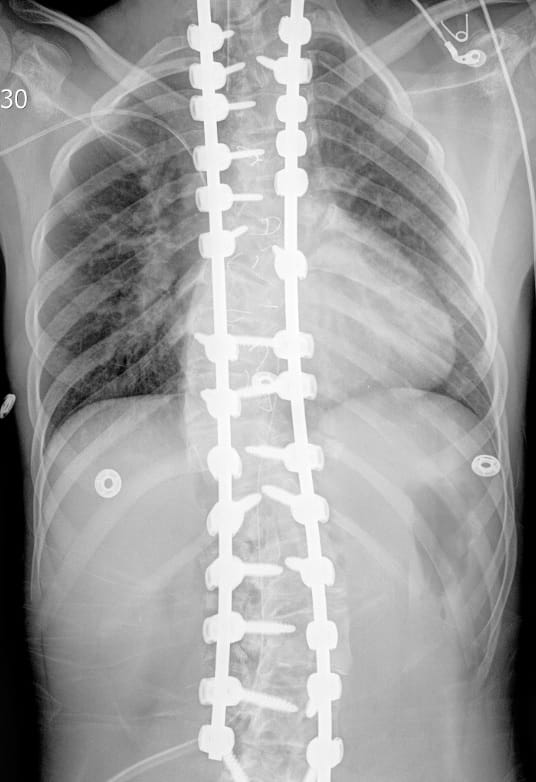

The young University Hospitals Rainbow Babies & Children’s Hospital patient was the first at University Hospitals – and in Ohio – to undergo spinal fusion surgery using FIREFLY® Technology. Firefly provides 3D-printed guides for pedicle screw navigation that mechanically constrain the drill and tap to follow preselected pathways. Using Firefly makes for extremely accurate screw placement. It also makes spine surgery safer and uses much less radiation.

Christina Hardesty, MD, Pediatric Orthopaedic Surgeon, UH Rainbow Babies & Children’s Hospital and UH Ahuja Medical Center; Assistant Professor, Orthopaedics and Adjunct Professor, Pediatrics, Case Western Reserve University School of Medicine, worked with Firefly engineers to turn CT scans of the young patient’s spine into an anatomically matched 3D-printed model. The 3D model, or guide, gave Dr. Hardesty a clear picture of the patient’s spine to help her prepare for surgery. When Dr. Hardesty placed the guides on the patient’s spine during surgery, she could see precisely where to place rods and screws – despite the twists and turns of the patient’s spine.

Using Firefly, Dr. Hardesty was able to correct her patient’s spine from about a 90-degree curve to a 20-degree curve. “That would not have been achieved had I not been able to put two screws in at every level,” she says. “Without Firefly, I couldn’t have done that.”

Dr. Hardesty says employing the technology also shaved at least an hour off surgical time and helped speed the patient’s recovery. Her young patient walked upright the day after surgery.